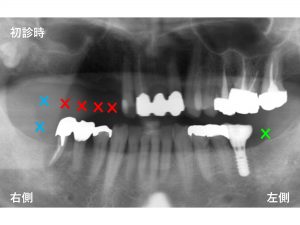

この患者様は、左側も欠損全てにインプラントを行っているわけではありません。

(下顎左側のインプラントは他の歯科医院ですでに行われていました。

当医院でのインプラント治療ではありません)

下顎左側一番奥歯には、インプラント治療は行われていませんでした。(✖︎:緑印)

おそらく治療費用の問題もあったのかもしれません。